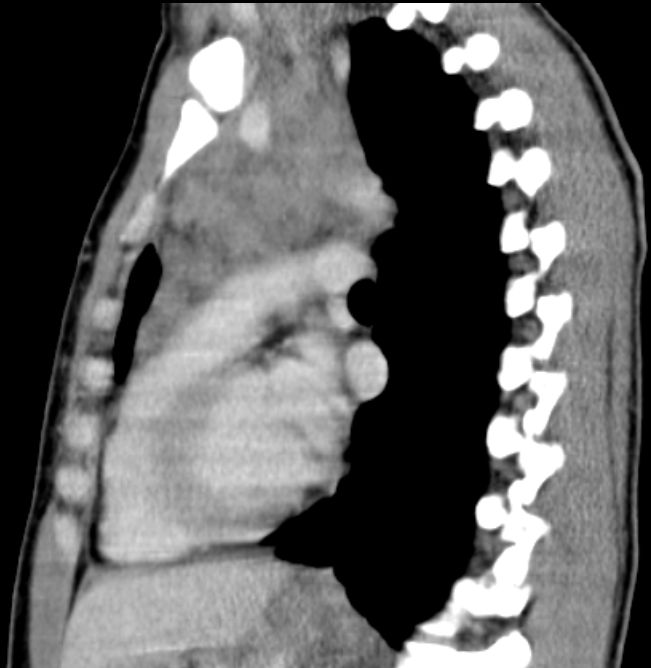

| thorakal | 21-jährige Frau mit Morbus Hodgkin mediastinal und zervikal beiderseits. Stadium IIA, Risikofaktor: hohe BSG. Noduläre Sklerose. | ||